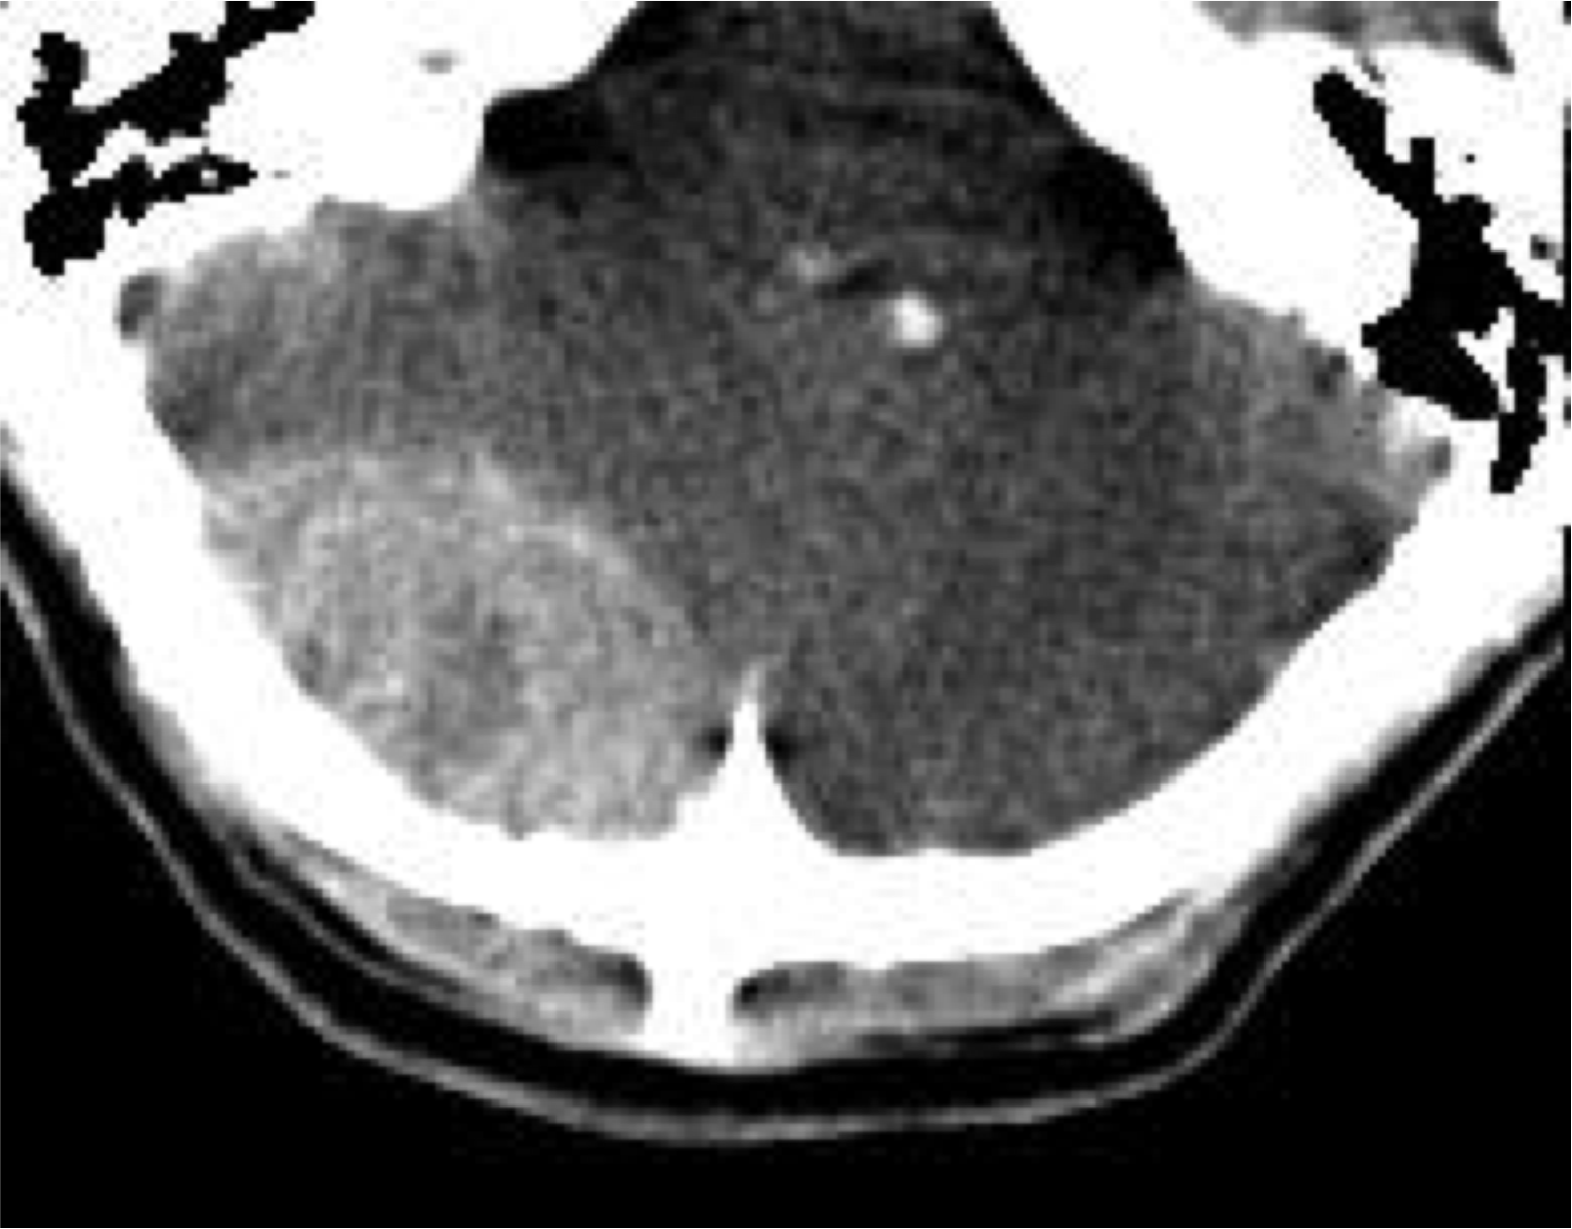

- Comparado con la HSA por rotura de aneurisma, la de origen postraumático suelen se de localización periférica, por encima de los hemisferios cerebelosos.

Hemorragia Intraventricular.